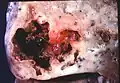

L'abcès pulmonaire est un type de nécrose liquéfiée du tissu pulmonaire et la formation de cavités (plus de 2 cm)[1] contenant des débris nécrotiques ou du liquide, causée par une infection microbienne.

Image de pathologie d'un abcès pulmonaire.

Un abcès sous-pleural.